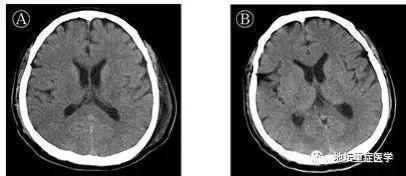

许先生1月24日以新冠肺炎、危重型、呼吸衰竭收入院。入院后给予联合干扰素雾化、抗病毒治疗,预防细菌感染,并给予中医辨证用药。未见好转,高热,乏力,呼吸困难逐渐加重。1月27日(起病第10天)胸部CT显示双肺磨玻璃密度影范围扩大,部分实变影。短暂予经鼻高流量吸氧,其呼吸窘迫无缓解,烦躁不安,呼吸50次/分,氧分压85%,在ICU进行气管插管,按照重度呼吸窘迫综合征(ARDS)的呼吸通气原则进行机械通气。治疗96小时后(起病第14天),患者出现颌面及口角频繁抽搐,伴持续呃逆,医生查体发现颈抵抗阳性,双侧瞳孔等大等圆,对光反射迟钝,四肢肌张力升高,双侧膝反射亢进,双侧巴氏征及踝阵挛阳性,头颅CT颅内未见异常,测脑脊液压力大于330mmH2O,脑脊液外观无色清亮,生化检测无异常。北京地坛医院重症医学科、检验科及中国疾控中心传染病所联合工作组对采集的脑脊液标本进行宏基因组二代测序、鉴定可能的感染病原体过程中,排除了其他病原体,获得了SARS-CoV-2病毒基因组序列。通过基因测序证实脑脊液中存在SARS-CoV-2,临床诊断病毒性脑炎。

医护人员经过对其14天机械通气和甘露醇控制颅压、咪唑安定控制抽搐、丙种球蛋白及甲基强的松龙抗炎等针对病毒性脑炎的处理,观察患者肺病影像学逐渐好转,神经系统症状消失。2月10日(起病第24天)在充分评估患者呼吸及神经功能后拔出气管插管,给予鼻导管吸氧。2月18日(起病第32天)转出重症监护室,到新冠确诊病房继续接受治疗。